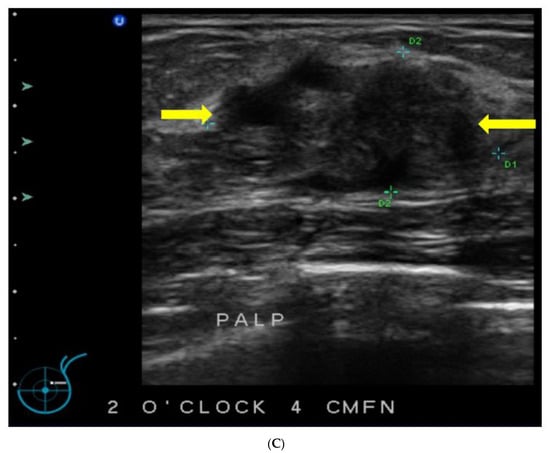

5. Ultrasound (US)